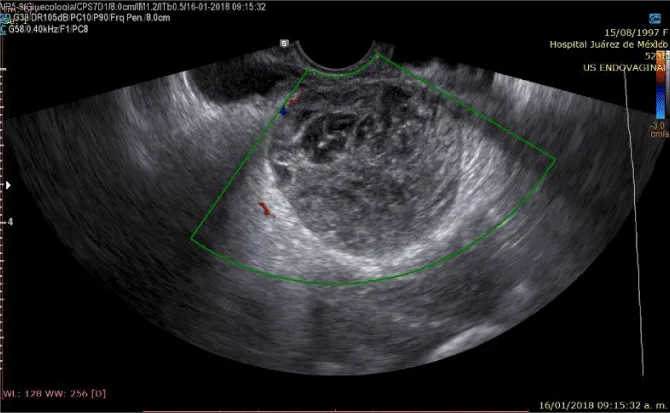

A 20-year-old married woman, with no history of pregnancy, who was admitted to the hospital for colicky abdominal pain in the right iliac fossa with radiation to the right iliac fossa from moderate to severe with Visual Analogue Scale with nausea and vomiting treated with analgesics presenting slight improvement; It is requested, quantification of the beta fraction of gonadotropin with figures of 112,337 mIU/mL and pelvic ultrasound with a report of a complex cyst of the right ovary without evidence of free fluid in the cul-de-sac; in relation to probable dysgerminoma or tumor of etiology to be determined; the hematic biometry with hemoglobin of 15.8 and hematocrit of 45, platelets of 313,000, leukocytes of 11,300 and 2 bands; reason for which she is referred to Hospital Juárez de México and once hospitalized; on August 18, 2017; she presents low-cost symptoms; and the studies are repeated quantification of beta fraction of Human Chorionic Gonadotropin (hGC) greater than 5,000, hemoglobin of 18 grams, hematocrit of 47%, leukocytes of 12,000, platelets of 367,000, lactic dehydrogenase of 473, direct bilirubin of 0.8 and the 2.3 total; normal liver transaminases; Ultrasound reports uterus in anteversion of 79x26x31mm, homogeneous myometrium, endometrial thickness of 7.9mm and right annex with lesion of 114 x83x79mm and total volume of 394cc, heterogeneous with linear images in its interior punctiform, the ultrasound diagnosis was, probable right annex teratoma tumor cystic.

On physical examination, the patient with generalized pallor of the skin and integuments, hypotensive, tachycardic, diaphoretic, without cardiorespiratory compromise, globose abdomen due to abundant adipose panniculus, perstalsis present, pain on palpation in the right iliac fossa on bimanual touch, the uterus is delimited 8x5 cm, right annex, 12x9 cm adnexal tumor, irregular, firm, pain on cervical mobilization, with spotting-shaped transvaginal hemorrhage, extremities without edema, normal tendon reflexes. According to the clinical presentation, imaging studies, on suspicion of ruling out ectopic pregnancy, an exploratory laparotomy was performed, with findings of the right annex of 20x15 cm adhered to the uterus and sigmoid rectum without evidence of hemoperitoneum and a right salpingo-oophorectomy was performed for probable right ectopic pregnancy with hematic loss due to the surgical procedure of 40cc and sent to pathology for definitive histopathological study, during follow-up a control gonadotropin quantification was requested with the last report of 1 103 918.7 mUI/mL. The histopathological results of the macroscopic surgical specimen were right salpingo-oophorectomy, with choriocarcinoma with extensive necrosis, 1 cm tumor extension to the ovarian surface not identified, lymphovascular invasion present and free surgical margins of the residual ovarian tumor with cystic follicles, Figure 1 and the report microscopic, Figures 2-4. A new hCG quantification is performed, negative head tomography and chest tomography with probable metastasis due to pulmonary nodule, in abdomen and pelvis, presence of peritoneal carcinomatosis, with free fluid and lumbar puncture reports negative for malignant cells and chemotherapy based on cisplatin and etoposide 5 sessions and the patient is disease-free after two years of follow-up.